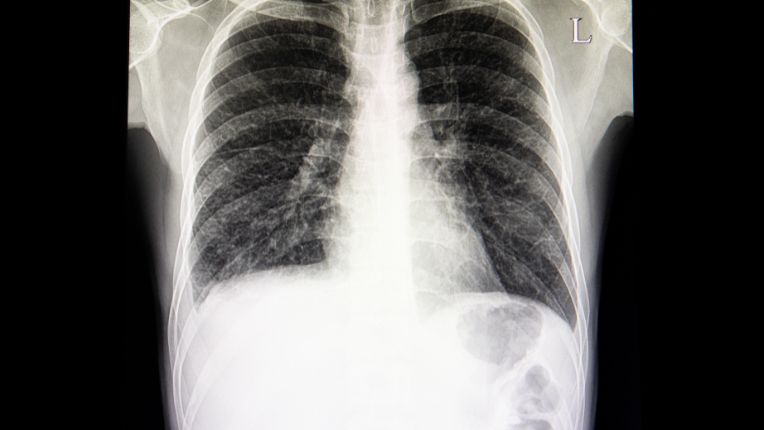

Qu’est-ce que la plèvre ?

Les poumons sont entourés chacun par une membrane la plèvre, constituée de feuillets qui contiennent le liquide pleural. Ce liquide sert à éviter que les poumons ne frottent contre la paroi de la cage thoracique quand on respire. Le mésothéliome le plus courant s’appelle le mésothéliome pleural malin. En France, on compte environ 1 100 nouveaux cas par an. Ce cancer touche surtout les hommes. Malheureusement, c’est une maladie grave très souvent en lien avec l'exposition à l'amiante.

La pneumologie est la spécialité qui s’occupe des poumons et de la respiration. Le pneumologue s'intéresse à l'appareil respiratoire. Il ou elle est amenée à prendre en charge des pathologies comme : l’asthme, les bronchites, l'apnée du sommeil, la broncho-pneumopathie chronique obstructive ou BPCO, la pleurésie, la broncho-pneumonie, les maladies infectieuses comme la tuberculose ou la Légionellose, les tumeurs, l'insuffisance respiratoire...

En cas de pathologie de la plèvre (douleur thoracique, épanchement pleural, pleurésie, pneumothorax ou suspicion de tumeur pleurale), il faut consulter un pneumologue, le spécialiste des poumons et de la respiration. C’est lui qui pose le diagnostic, prescrit les examens (radio, scanner, ponction) et propose un traitement. Si une cause cancéreuse est suspectée, un oncologue peut être impliqué. En cas de besoin chirurgical, comme une biopsie ou une intervention sur la plèvre, un chirurgien thoracique prendra le relais. Pour les cas complexes, plusieurs spécialistes peuvent travailler ensemble pour proposer une prise en charge complète.